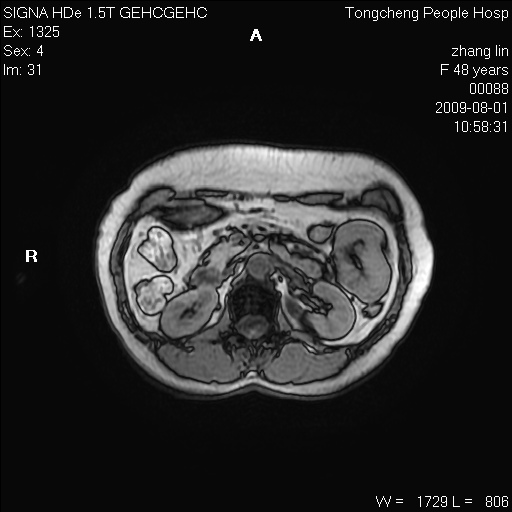

女,48岁。健康体检,彩超发现右肾占位性病变。平素健康。

临床诊断:右肾占位性病变,性质待定(囊肿?肿瘤?)。

上中腹部mr平扫+增强扫描,图像如下:

右肾上极见一类圆形病灶,t1wi呈等信号t2wi呈等高混杂信号,三期增强无强化,边界清---考虑囊肿出血。

同反相位均表现为等信号,病变无强化,考虑含蛋白的囊肿可能,弥散加权相或许有些帮助,